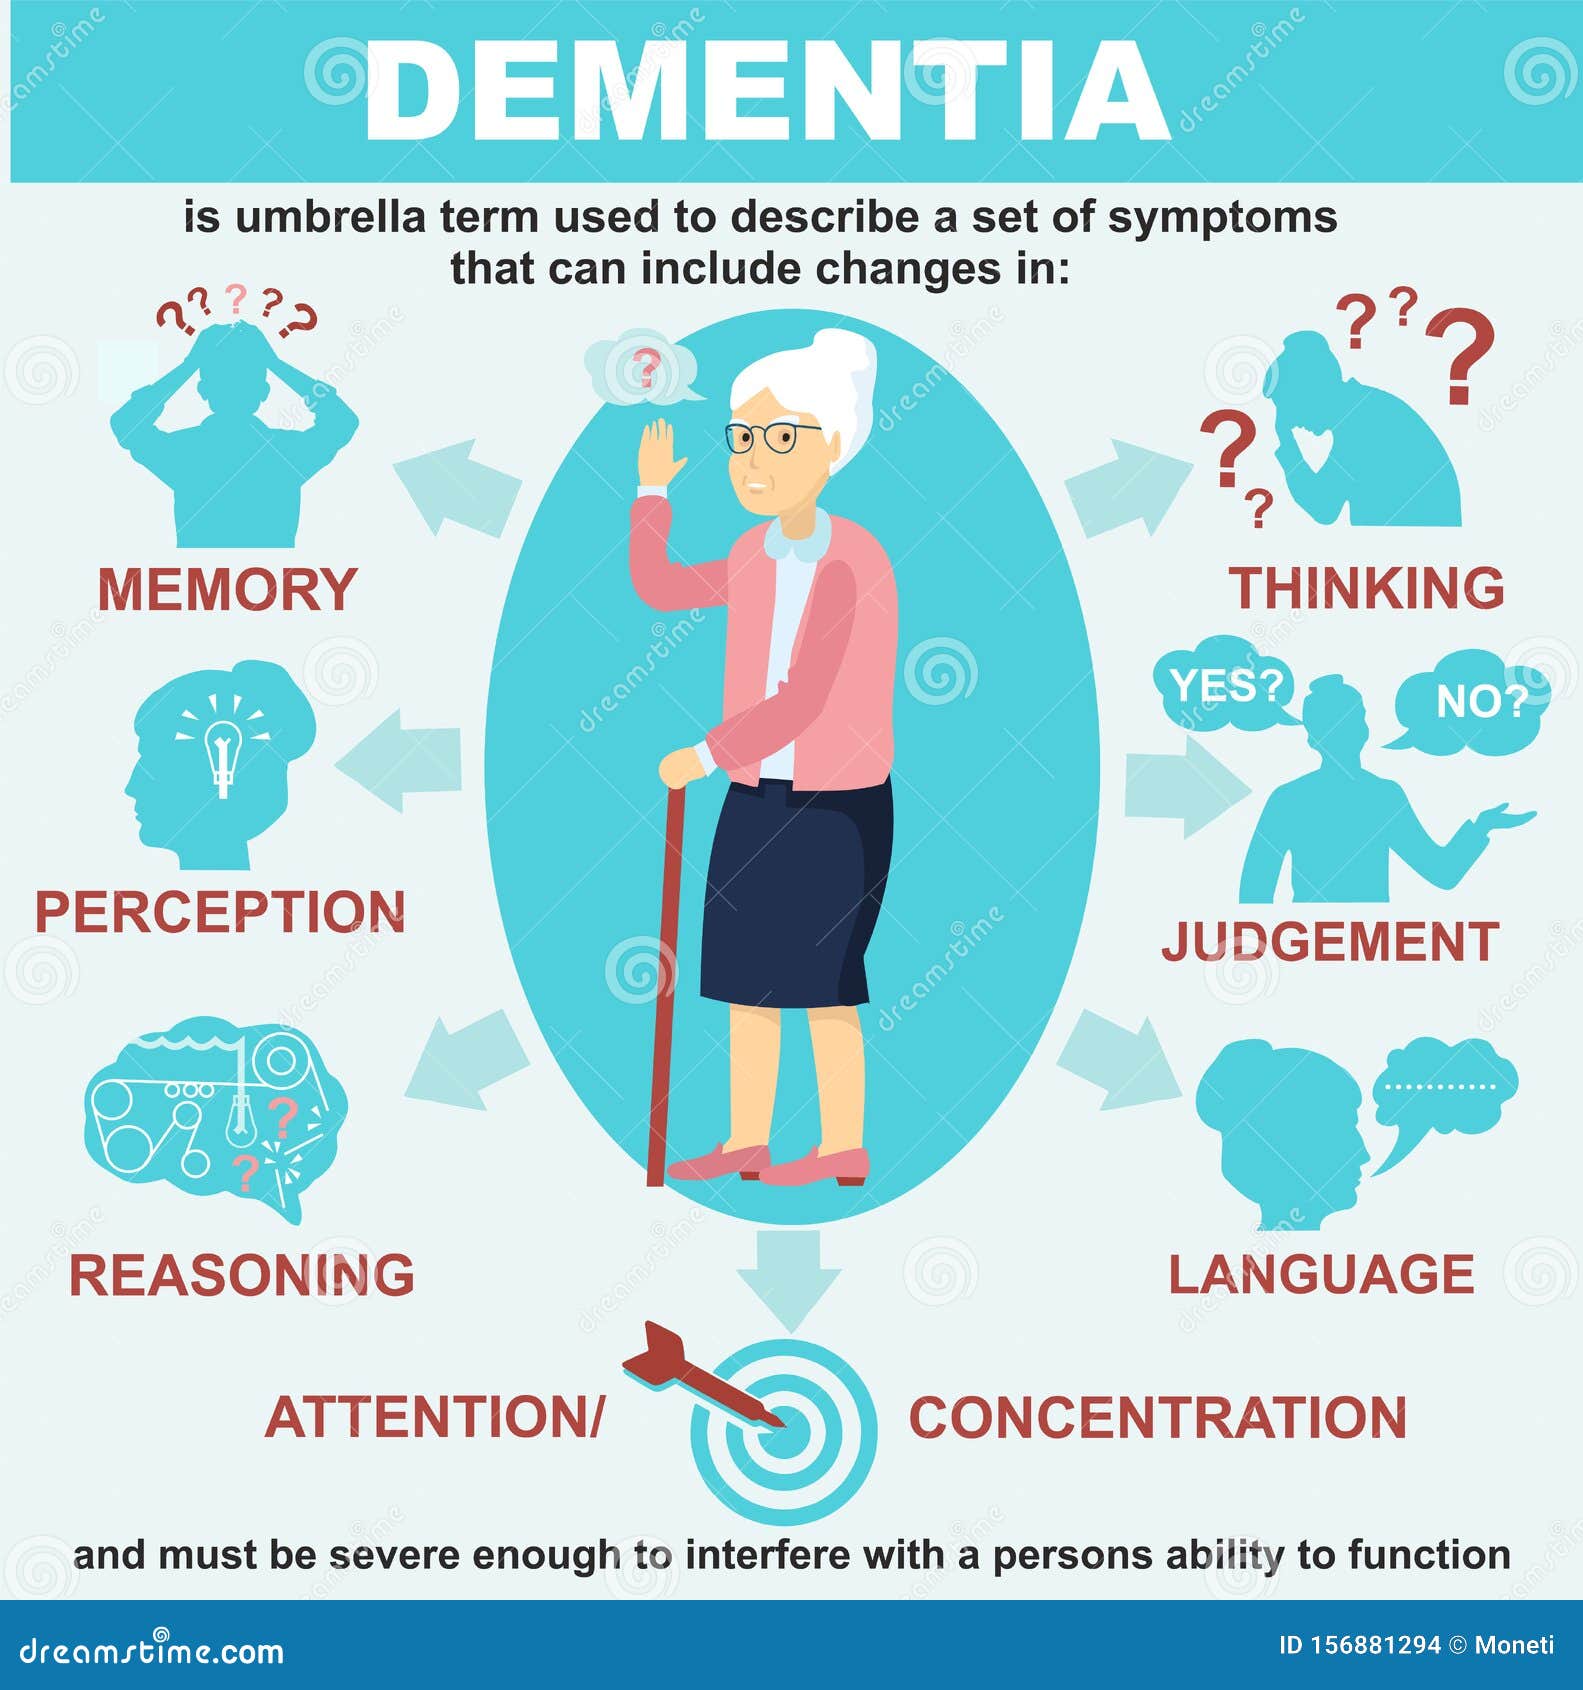

Dementia is an umbrella term. It describes the symptoms that occur when …